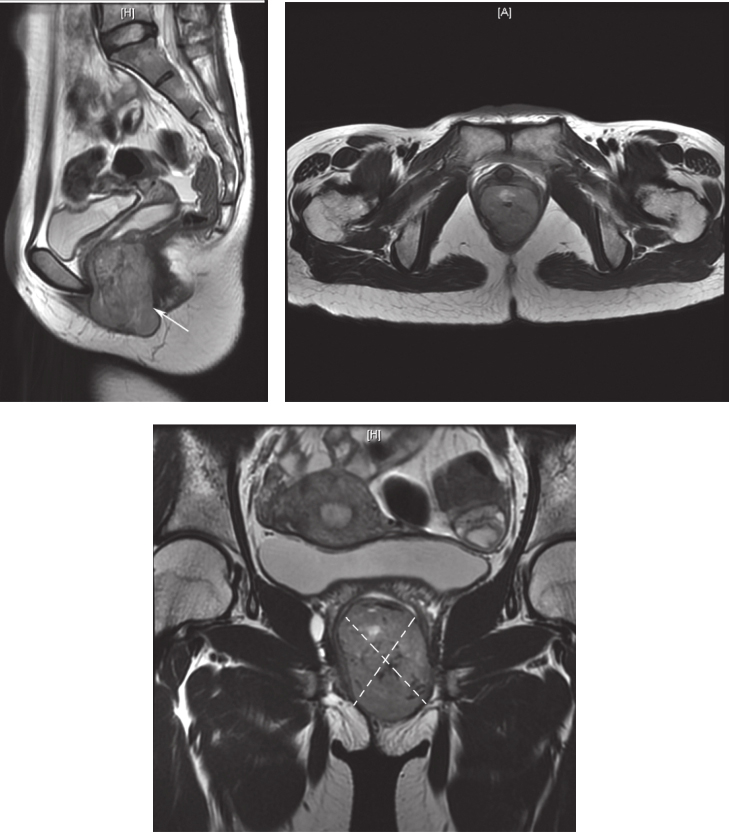

患者,女性,33岁,于2016年4月8日因“发现会阴部肿物1年半”就诊。患者于2014年10月体检发现“左侧阴道内壁囊肿”,无疼痛,无接触性出血,未行治疗。2015年10月时感觉经期阴道左侧坠胀感,行超声检查考虑“左侧前庭大腺囊肿”,予中药治疗,效果不佳。2015年11月自觉肿物增大、向外膨出,伴尿细、排尿不尽感,未见异常分泌物,行妇科超声检查示:阴道壁外口左侧见一囊实性结构,大小约2.3cm×2.1cm×2.3cm,边界清楚,内透声差,可见密集点状回声。2016年2月自觉肿物增大伴疼痛、会阴区红肿,于外院以“前庭大腺囊肿伴感染”收住院,并行抗感染治疗,自觉症状稍缓解。2016年3月于外院行前庭大腺囊肿切除术,术中发现囊实性肿物,以实性成分为主,考虑肿物性质不明确,遂暂停切除术,行囊性成分穿刺吸取血性液体3ml,送细菌培养阴性。术后持续有血性渗出,自觉肿物变大,行抗感染治疗后疼痛稍缓解。行超声引导下经会阴穿刺活检术,病理示:梭形细胞肿瘤,细胞中度异型,核分裂象易见(18 个 /50 HPF),免疫组织化学染色:CD117(+),CD34(+),S-100(-),Ki-67(Li:10%~20%),ER(-),PR(-),考虑胃肠间质瘤(高危)可能性大。穿刺组织基因检测:c-KIT基因11外显子缺失突变(c.1670-1675delGGAAGG.)。术后患者自觉肿块明显增大,疼痛加重。完善盆腔MRI(图1):直肠下段与阴道间见类椭圆形混杂软组织信号影,最大截面约5.7cm×3.7cm,增强扫描见不均匀强化,病变与直肠前壁、阴道后壁均分界不清,邻近组织受压移位;阴道上段梗阻积液。

图1 首诊盆腔MRI表现

引自:胃肠间质瘤典型病例诊治与解析.第1版.ISBN:978-7-117-30146-6.主编:陶凯雄 曹 晖